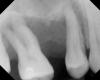

А это верхняя четвёрка. Месяц назад был сильный флюс, потом образовался свищ в десне и до сих пор там покраснение и воспаление. Немного шатается.